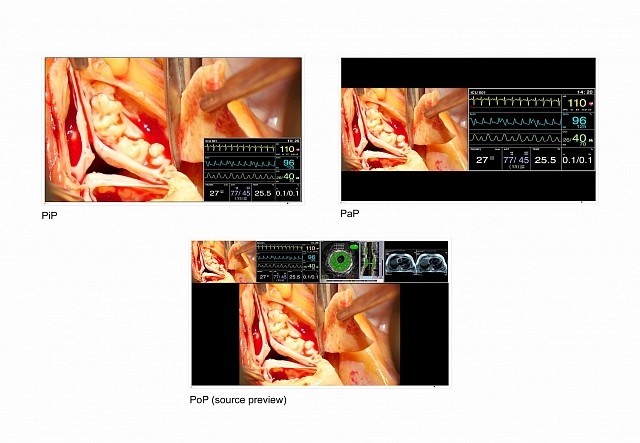

- Flexible image arrangement thanks to the Picture-in-Picture (PiP) and Picture-at-Picture (PaP) functions